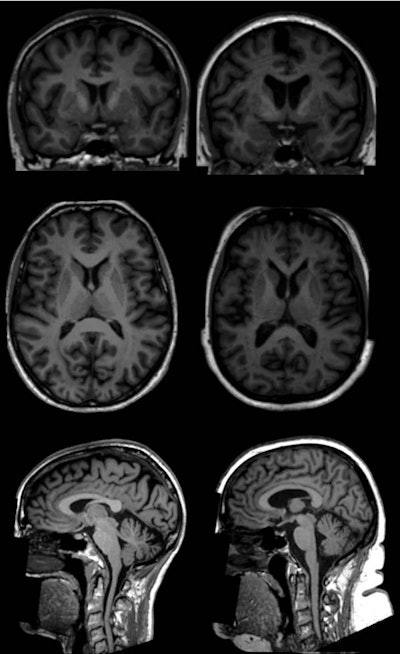

To test their theory, they perused data of more than 500,000 participants in the U.K. Biobank study, which began in 2006 to learn more about the genetic and environmental factors that influence disease. From that pool, 12,087 participants with a mean age of 62 (± 7.3 years; range, 45 to 76 years) met the inclusion criteria. Of those subjects, 6,381 (53%) were women and 5,706 were men (47%). Brain scans were acquired on a 3-tesla system (Magnetom Skyra, Siemens Healthineers) with a standard 32-channel radiofrequency receiver head coil.

The brain imaging protocol included 3D T1-weighted diffusion-tensor imaging (DTI), which acquired fractional anisotropy measurements to determine white matter integrity and water molecule diffusion. In addition to total body fat calculations, volumetric measures were performed to gauge overall brain volume, gray and white matter volumes, subcortical gray matter structure volumes, and regional cortical volumes.